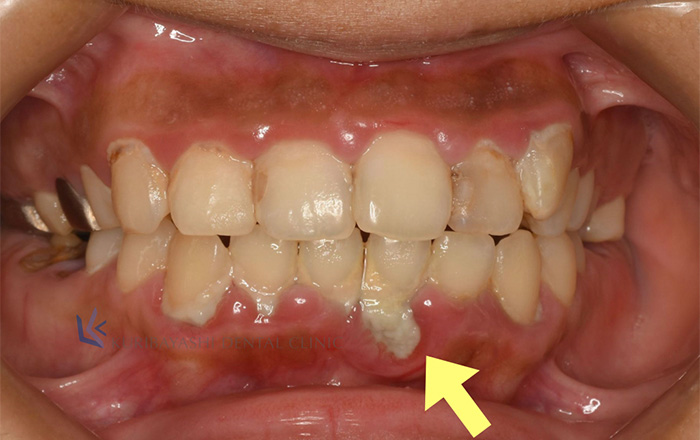

バイ菌が残りやすい部分は、

1)歯と歯ぐきの境目

2)歯と歯の間

が多いです。

溜まったバイ菌のかたまりの歯垢(プラーク)がそのままになっているとだんだんと石灰化します。

2~3日で石灰化し始め、放っておくと歯石へ変化していきます。